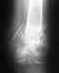

В декабре ребенок попал в больницу с первичным диагнозом периостит левой большой берцовой кости.

Ушибов и травм не было.Ширина ноги увеличилась на 1,5 см. Сделана трипанобиопсия(ничего не показало, ренген, радиоизотопное исследование (ничего не показало, энцефалограма (обострение сидящего нерва справа и слево) компьютерная томография и МРТ ничего не показала. Боли продолжаются постоянно особенно при нагрузках и холоде. В ЦИТО на консультации объявили саркома или осьтемилит. Что необходимо сделать чтобы установить окончательный диагноз?